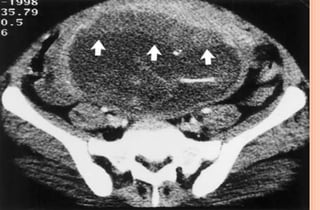

PHOTOS OF CT EVALUATION OF

PREGNANT WOMAN WITH TRAUMA– CT

SCANS DONE AS A PART OF INVESTIGATIONS

DONE IN EMERGENCY --- MATERNAL HEAD

AND ABDOMEN AS PER NEED OF INDIVIDUAL

CASE ---WITHOUT FEAR OF X RAYS

EXPOSURE TO FETUS IN UTERO

PHOTOS OF CTEVALUATION OF PREGNANT WOMAN WITH TRAUMA– CT SCANS DONE AS A PART OF INVESTIGATIONS DONE IN EMERGENCY --- MATERNAL HEAD AND ABDOMEN AS PER NEED OF INDIVIDUAL CASE ---WITHOUT FEAR OF X RAYS EXPOSURE TO FETUS IN UTERO